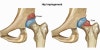

1. Cam impingement : Femoral cause(Femoral waist deficiency)

이른바 ‘pistol grip deformity’와 같이 대퇴골두의 모양이 구형이 아닌 것으로 인한 ‘cam 효과’ 때문에 고관절 운동시 대퇴골두의 튀어나온 부분과 비구연(acetabular rim)과의 충돌이 발생하게 됩니다.

돌출된 대퇴골이 비구내로 들어오면서 outside-in의 형태로 먼저 비구연골이 abrasion되고, 계속된 충돌에 의해 전상방 비구순 및 연골하골의 손상이 생기게 됩니다.